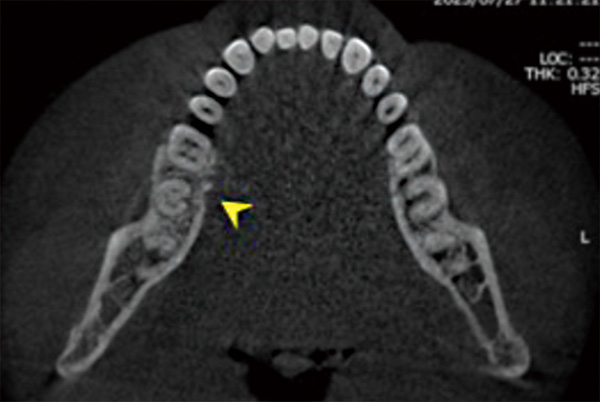

右下第一大臼歯舌側に骨露出を伴わない潰瘍を認めます。

歯科用CTでは同部の歯槽骨の一部喪失(矢印)が確認されます